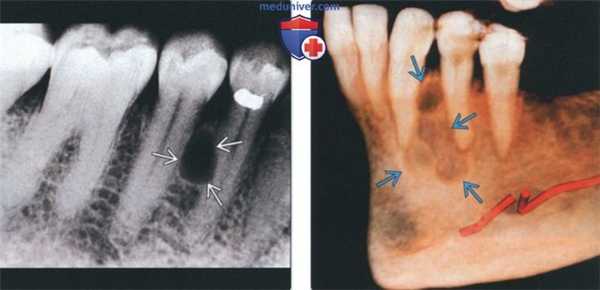

(Слева) На периапикальной рентгенограмме нижней челюсти справа между первым и вторым премоляром (наиболее типичная локализация) определяется боковая периодонтальная киста. Обратите внимание, что киста имеет классический вид слезы.

(Справа) На сагиттальной трехмерной реконструкции (КЛКТ) между первым премоляром и клыком нижней челюсти определяется многокамерное объемное образование. Была выполнена биопсия, подтвердилась гроздевидная одонтогенная киста (ГОК).

(Слева) При аксиальной КТ в костном окне визуализируется мелкая периапикальная радикулярная киста возле корня центрального резца верхней челюсти справа. Признаков периостальной реакции или наличия объемного образования в мягких тканях за пределами челюсти не определяется.

(Справа) При сагиттальной КТ у этого же пациента визуализируется периапикальная киста и стоматологическая амальгама в этом же зубе.